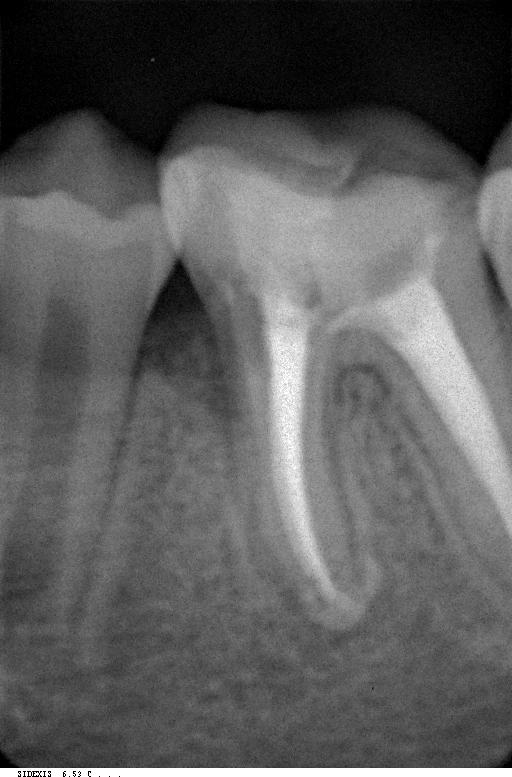

Вот такие коварные восьмые, а иногда и девятые маляры залегают в толщи кости.

Показания к удалению зубов мудрости:

1. Аномальное анатомическое положение в ряду -в некоторых случаях

третьи моляры могут расти под наклоном в сторону горла, щеки или языка,

это вызывает травмы слизистой оболочки рта, которые в свою очередь

приводят к язвам ;

2. Возникновение кариеса и периодонтита. Восьмерки очень сложно чистить

из-за дальнего расположения, вследствие чего появляется кариес, а

зачастую они уже имеют поврежденную эмаль при прорезывании. Кариес

быстро перемещается на соседние зубы и поэтому затягивать с визитом к

нам для оказания медицинской помощи ни в коем случае нельзя.

Как происходит процесс удаления зуба мудрости? В первую очередь перед процедурой наш дантист сделает рентген, чтобы определить местоположение и особенности строения зуба. Сама операция проходит под местной анестезией, и мы Вас уверяем что Вы даже не почувствуете укола. При прорезовшемся зубе после действия обезболивающего врач при помощи специальных инструментов извлечет зуб и наложит швы. Длится такая операция несколько минут , но стоит заметить, что верхние восьмерки как правило удаляются быстрее, потому что у нижних зубов корни имеют менее крепкую и извилистую структуру.

У пациентов, помимо прорезыванных зубов мудрости, встречаются и так называемые ретинированные, это те которые полностью скрыты под десной, а также дистопированные - с неправильным расположением в зубном ряду. Чаще всего встречаются ретенированные и дистопированные зубы одновременно. Следует также выделить полуретинированные восьмерки - это зубы , которые появились из десны не до конца. Зачастую в том варианте, когда видна только часть зуба, между ним и десной образуется небольшой карман- капюшон, и это образование вызывает гнойное воспаление - перикоронит. В запущенных случаях, помимо болевых ощущений в самой зоне зуба перикоронит может вызывать сильнейшие головные боли и повышение температуры.